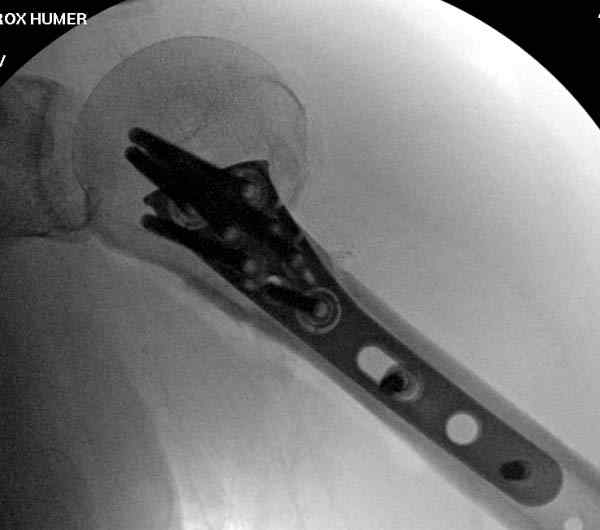

Пациентка Б.1953 г.р., врач-терапевт. Травма 27.11.08г. Падение с высоты роста. Выявлен закрытый не осложненный оскольчатый перелом хирургической шейки левого плеча со смещением. 02.12.08г. оперирована. Выполнена открытая репозиция и остеосинтез пластиной LCP Деост с дополнительной фиксацией отдельно лежащего фрагмента винтом. Послеоперационный период протекал без особенностей, заживление раны первичным натяжением. Швы сняты через 10 дней. Иммобилизация левой верхней конечности клиновидной подушкой 4 недели. По окончании срока – рентген-контроль и умеренная разработка плечевого сустава. В течении месяца функция левого плечевого сустава восстановилась удовлетворительно: поднятие руки до 110 гр., отведение - 90 гр. и до 110 гр. отведение с лопаткой. Отведение руки назад – 20 гр. Наружная и внутренняя ротация – 20 гр. Пациентка по настоянию самостоятельно вышла на работу. 27.03.09 при контрольном осмотре жалоб не предъявляет, болевой синдром в левом плечевом суставе отсутствует. Отведение плеча активно до 90 гр, пассивно с лопаткой до 110 гр., поднятие – 110 гр, отведение назад 20 гр, наружная и внутренняя ротация по 20 гр. На контрольных рентгенограммах отмечается смещение металлоконструкции, ротация головки плеча с приведением дистального отломка на 13 гр. и смещением к зади на 30 гр. Рентгенограммы прилагаются. Ваш взгляд на дальнейшую тактику лечения пациентки?

Ни какой миграции и смещения пластины нет, это изначальные смещения при остесинтезе.

Нет аксиальной проекции сразу после вмешательства. Возможно, никакого значительного смещения нет, все осталось так, как первично сопоставили...и,

Уважаемый Евгений, похоже, что первый и второй Р-снимки выполнены несколько в разных положениях(ротация) плечевой кости, в связи с этим создается впечатление смещения пластины. Остеосинтез выполнен при угловом смещении отломков.Таковым и остался. Данная ситуация была бы очевидна гораздо раньше, если бы при контрольной Р-графии были выполнены снимки в 2-х проекциях.(Не в обиду, сам иногда выполняю только один).

Рентгенограммы действительно с дефектом укладки, но интраоперационная репозиция, можете поверить, была удовлетворительная как в акcиальной, так и в сагиттальной плоскостях. Интраоперационная рентгенограмма прилагается, хотя укладка тоже на ахти. По тактике - разделяю Ваше мнение об отсутствии необходимости реостеосинтеза, а тем более об эндопротезировании, хотя это все было предложено пациентке ведущими ортопедами-травматологами России.